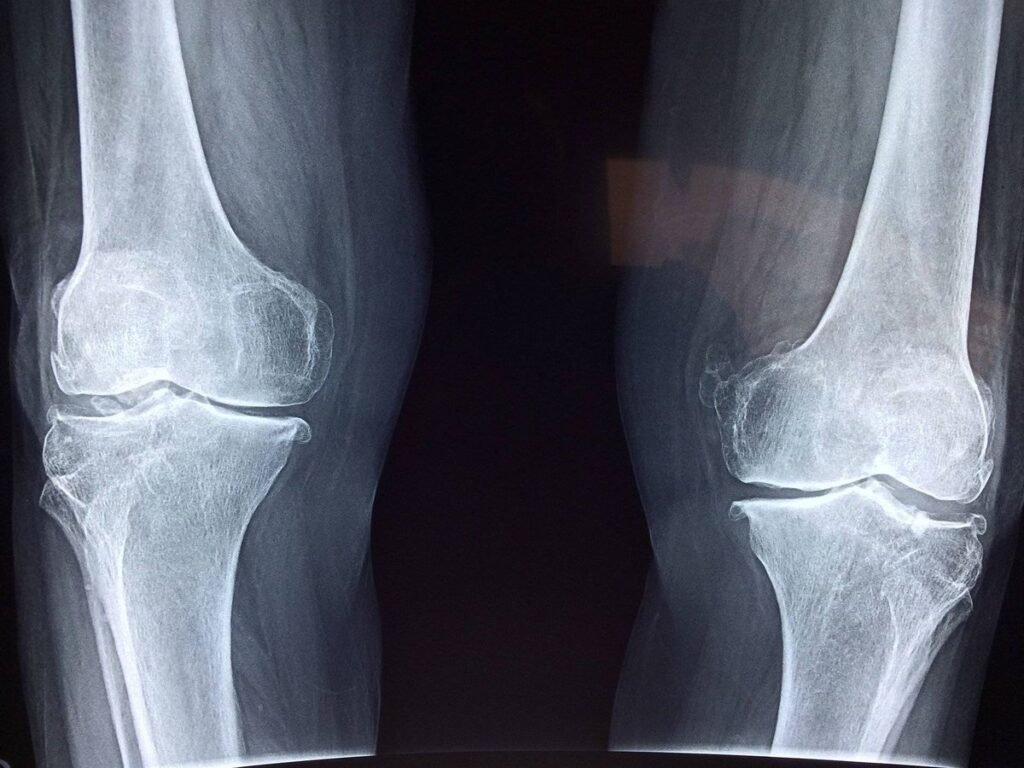

En un hito para la ciencia y la medicina argentina, un equipo de investigadoras de la Universidad Nacional del Noroeste de la Provincia de Buenos Aires (UNNOBA) ha logrado un avance prometedor en el campo de la regeneración ósea. A través de la startup MesencHyal-T, han diseñado una terapia innovadora que combina células madre mesenquimales del cordón umbilical con ácido hialurónico para reparar huesos que no logran consolidarse por sí solos.

Este proyecto, que requirió de diez años de trabajo científico riguroso, ha demostrado su potencial en pruebas in vitro y en modelos animales. Los resultados son contundentes: no solo se logró la regeneración del hueso, sino que el tejido reparado exhibió una calidad superior. Las pruebas mecánicas mostraron que los huesos tratados con esta terapia podían soportar mayor peso, con una combinación ideal de rigidez y flexibilidad.